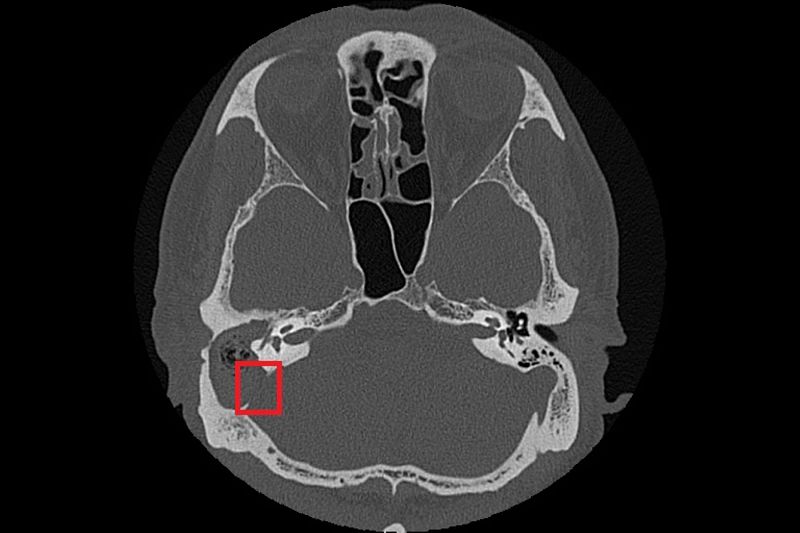

由於膽脂瘤多發生在中耳或接近顱底的位置,一旦形成,可能影響聽力與神經功能,其分泌物亦容易滋生細菌,導致反覆感染;若未及時治療,可能引發暈眩,甚至因鄰近顱內而造成腦膜炎、腦炎或腦膿瘍。目前,手術切除是膽脂瘤根治的唯一方法,術前需以顳骨電腦斷層檢查評估膽脂瘤範圍及侵蝕程度;手術方式依病灶大小、位置,可能採耳內微創、耳前或耳後切開術,徹底清除膽脂瘤並重建受損結構。急性發炎期則需輔以抗生素控制感染,術後追蹤可降低復發風險,但膽脂瘤若已侵蝕骨質,仍需長期觀察。以張先生為例,雖前後接受過局部藥物、抗生素治療,但考量其慢性中耳炎併發膽脂瘤已破壞聽小骨、乳突及部分顱底骨質,因此需從耳後切開進入外耳道及中耳腔,打開耳後的乳突骨,將病變組織除去後,重建修復骨骼和軟組織缺口。